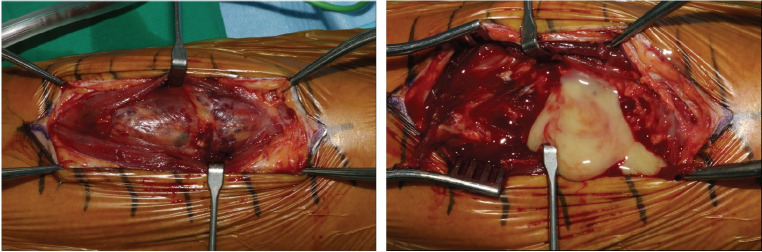

肌肉内血管瘤在肌肉骨骼疼痛鉴别诊断中很少被考虑,特别是在上肢,而且它们与肱二头肌内的感染性脓肿共存是非常罕见的。我们报告一个56岁男性二头肌肌内血管瘤伴脓肿形成的病例,其表现为左上臂疼痛和肿胀,热感,发红,肘关节屈曲和前臂旋后受限。c反应蛋白水平高(25.43 mg/dL),术前左上臂和肘部运动,视觉模拟评分为10分。x线平片示3个小静脉。磁共振成像显示二头肌左侧有一个界限不清的强化病灶(2.5×2.7×9.8 cm),病灶内t1加权信号增强,病灶内有一个小、圆、低信号强度的病灶,与肌内血管瘤一致,二头肌内侧有一个地理上的非强化区域,与感染性肌炎合并脓肿形成一致。我们进行了手术切除肌肉内血管瘤和引流脓肿在二头肌。术后5周,所有功能限制均消除,5个月随访无复发。

Intramuscular hemangiomas are rare in musculoskeletal pain differentials, especially in the upper extremities. We report a case of a 56-year-old male with an intramuscular hemangioma and abscess in the biceps brachii, presenting with pain, swelling, and limited elbow movement. High C-reactive protein (25.43 mg/dL) and visual analog scale score of 10 were noted. Radiograph showed 3 phleboliths. MRI revealed an enhancing lesion (2.5×2.7×9.8 cm) and abscess. We performed surgery for excision of the intramuscular hemangioma and drainage of the abscess in the biceps muscle. By 5 weeks post-surgery, all functional limitations had resolved, and no recurrence was observed at the 5-month follow-up.